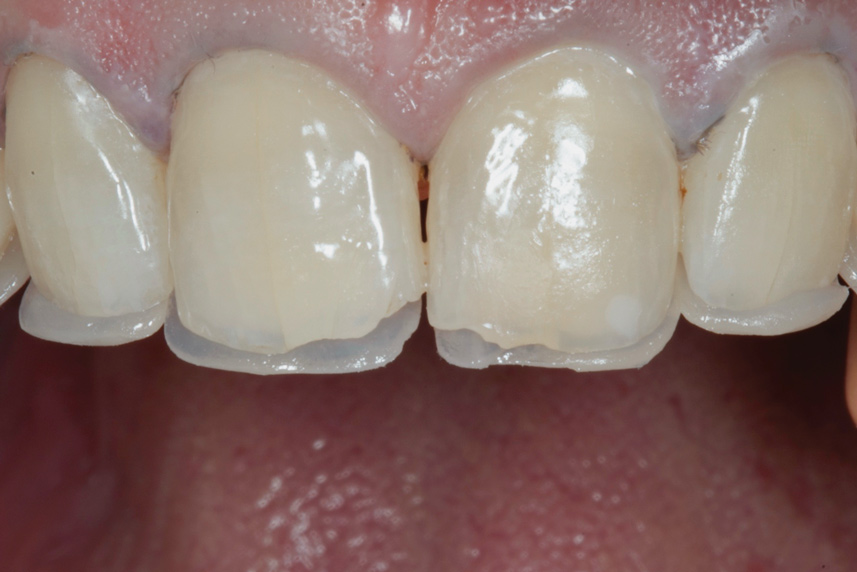

(1.) Preoperative smile photograph.

Figure 1

A 34-year-old male patient with no medical issues presented to the office with the chief complaint of a failing crown on tooth No. 12. The patient was also unhappy with his bite and the appearance of his teeth (Figure 1 and Figure 2).

The dentofacial examination revealed a low smile line with no incisor display when the lips were in repose. The anterior teeth were chipped and worn, and their overall color was darkened. The buccal corridors were deficient, and the failing crown on tooth No. 12 was visible in a full smile.